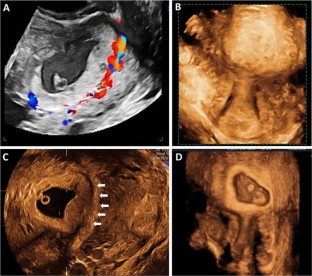

Cesarean scar pregnancy (CSP) is a rare kind of ectopic pregnancy implanted in the previous cesarean scar and has an increasing incidence over the past 30 years. As the suspicion is low, the diagnosis may be delayed or misinterpreted in ultrasound, leading to treatment strategies that might end up in uterine rupture or hysterectomy. The objective here is to review the ultrasound findings in CSP with varied presentations. Transabdominal and transvaginal sonography combined with color Doppler is a reliable tool for the diagnosis of CSP. When the gestational sac is seen in lower part of the uterine cavity, differentiation between threatened miscarriage, cervical pregnancy and CSP could be difficult. Not all cases of CSP present with typical ultrasound findings and a high index of suspicion is needed for diagnosis in these cases. An attempted curettage or MTP pill taken in an undiagnosed CSP often alters the typical findings. The possibility of CSP should also be considered in cases presenting with abnormal uterine bleeding and have a prior history of cesarean section. With lack of awareness about this condition, the diagnosis can often be missed either with MRI or in ultrasound. Correct interpretation and timely diagnosis save the mother from life-threatening complications and also preserves future fertility.

Fig. 2